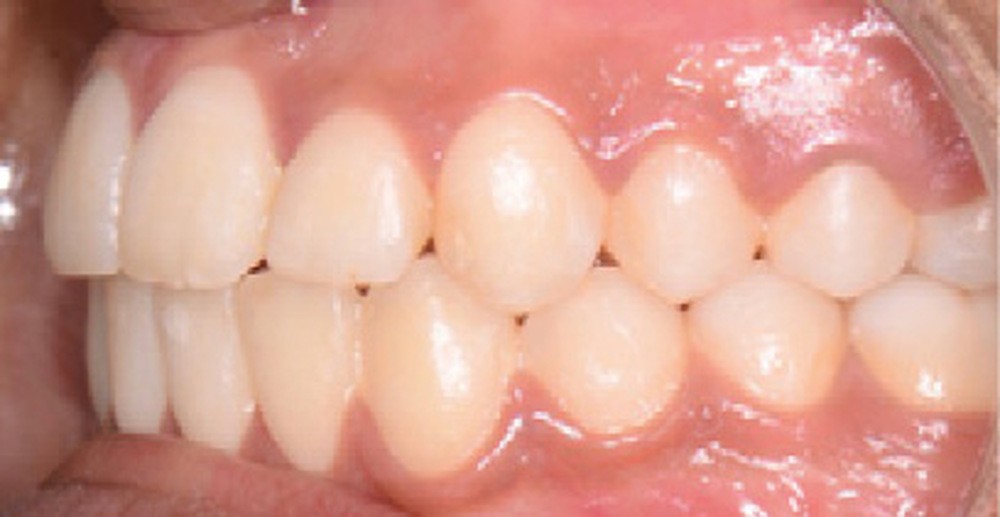

Le résultat de fin de traitement est satisfaisant. Le profil de la patiente est harmonisé. Une contention fixe mandibulaire et maxillaire de canine à canine est choisie.

La phase de préparation pré-chirurgicale a duré huit mois. La chirurgie a ensuite été reportée de trois mois par souhait de la patiente (départ en vacances puis volonté de réaliser la chirurgie durant des vacances scolaires). La phase de finition a été légèrement augmentée, du fait d’un mauvais port des élastiques de blocage par la patiente. Au total, le traitement a duré vingt-deux mois.